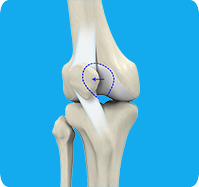

Knee Pain

Knee pain is a common condition affecting individuals of various age groups. It not only affects movement but also impacts your quality of life. An injury or disease of the knee joint or any structure surrounding the knee can result in knee pain. A precise diagnosis of the underlying cause is important to develop an appropriate treatment plan.

Any damage to the supporting ligaments may cause the patella to slip out of the groove either partially (subluxation) or completely (dislocation). This misalignment can damage the underlying soft structures such as muscles and ligaments that hold the kneecap in place. Once damaged, these soft structures are unable to keep the patella (kneecap) in position.

Patellofemoral instability means that the patella (kneecap) moves out of its normal pattern of alignment. This malalignment can damage the underlying soft structures such as muscles and ligaments that hold the knee in place. Patellofemoral instability can be caused because of variations in the shape of the patella or its trochlear groove as the knee bends and straightens.

Lateral patellar instability is defined as a lateral shift or displacement of the patella (kneecap) as a result of disruptive changes in the medial patellofemoral ligament (MPFL) and medial patellar retinaculum. Lateral patellar instability can be caused by variations in the shape of the patella or its femoral groove as the knee bends and straightens. Normally, the patella moves up and down within the femoral groove when the knee is bent or straightened.

Patellar Dislocation/Patellofemoral Dislocation

Patellar dislocation occurs when the patella moves out of the patellofemoral groove, (trochlea) onto the bony head of the femur. If the kneecap partially comes out of the groove, it is called subluxation; if the kneecap completely comes out, it is called dislocation (luxation).